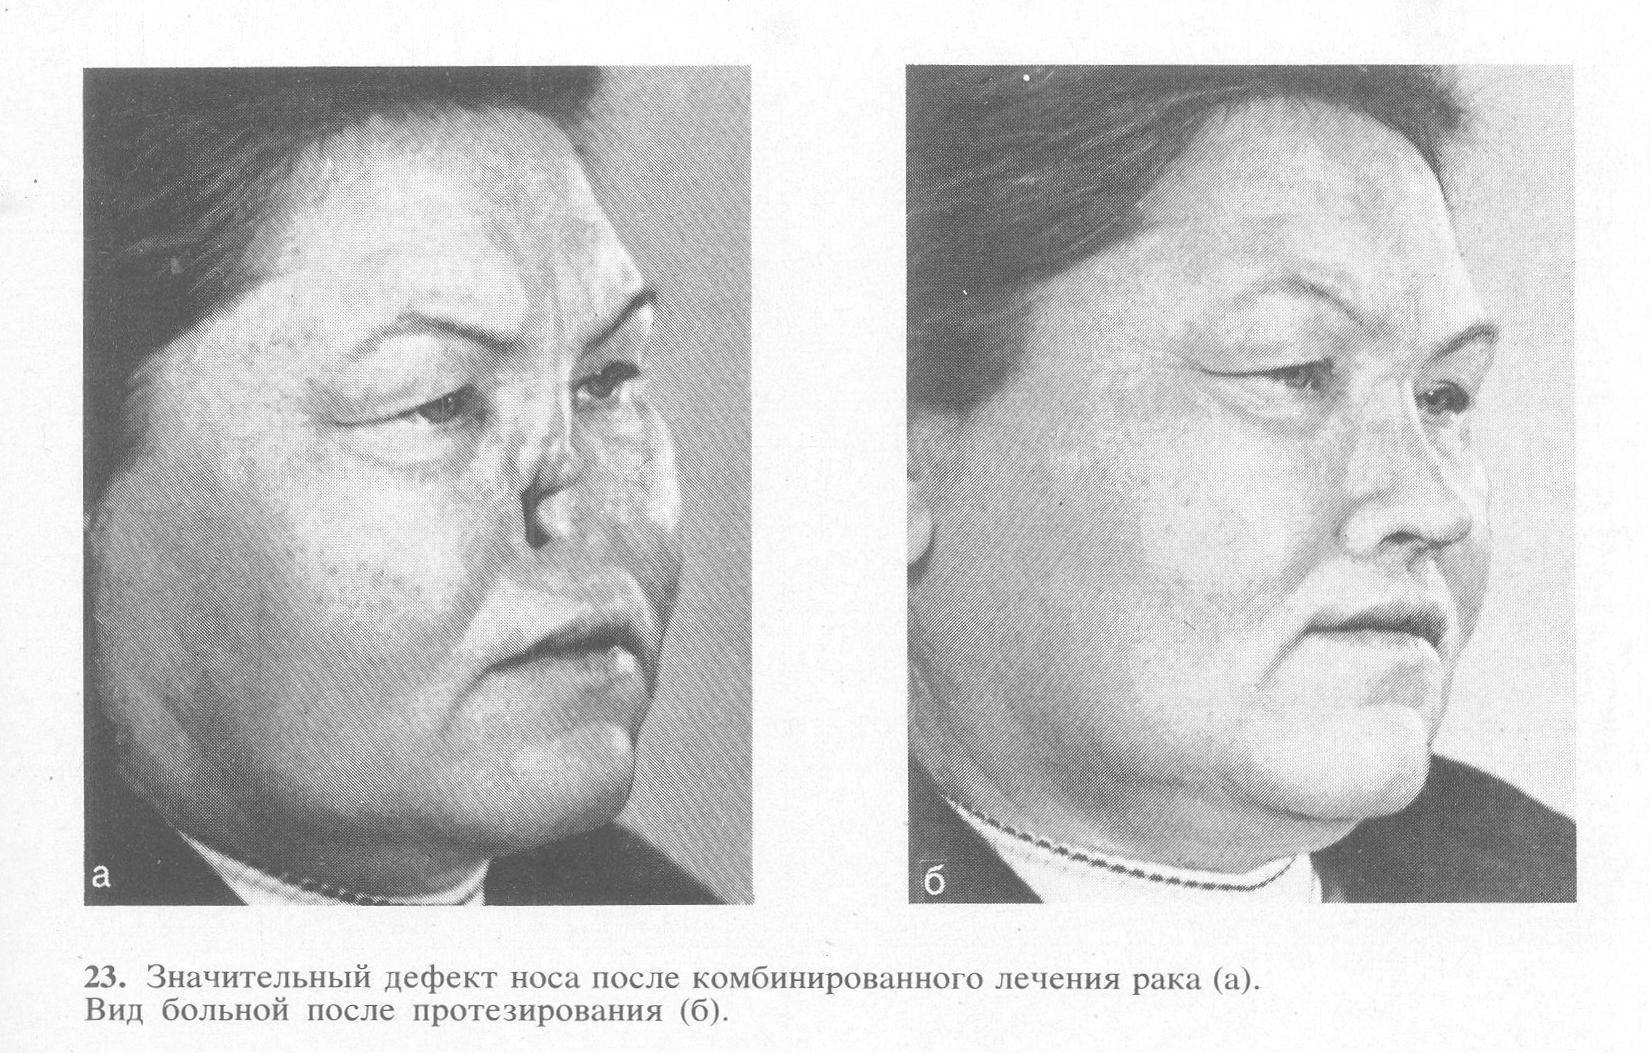

Фото раковой шишки на лице

Одной из наиболее распространенных локализаций раковых шишек является лицо. На фото вы можете увидеть различные типы раковых шишек, такие как базалиома, плоскоклеточный рак и меланома. Обратите внимание на характерные признаки каждого типа раковой шишки, такие как изменение цвета, формы и размера.